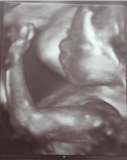

Profilbild Silas Rosenbaum

Silas Rosenbaum

* 24.01.2013 in Neckar Odenwald Kliniken Mosbach

† 24.01.2013